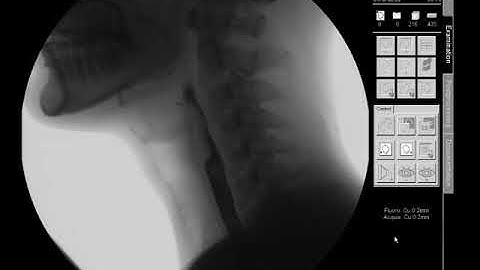

Swallow Study - Solid Texture/Cracker - Modified Barium Swallow Study (MBSS) Lateral View HD